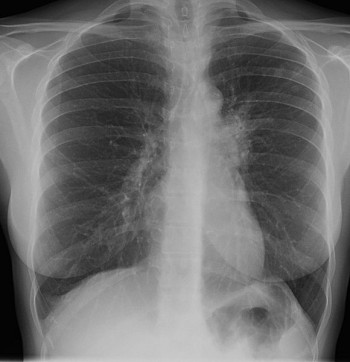

Două cazuri de TBC au fost descoperite la Colegiul Național „Ienăchiţă Văcărescu “ şi la Colegiul Naţional „Constantin Carabella “.

Este vorba despre o elevă de cala a XI-a, de de la Colegiul Național „Ienăchiţă Văcărescu “ şi o altă elevă de clasa a XII-a, de la Colegiul Naţional „Constantin Carabella “. În aceste condiţii, toţi cei care au fost în contact cu cele două persoane vor fi monitorizaţi şi trebui să-şi facă analizele specifice. Şi nu sunt puţini. E vorba de câteva sute de elevi şi profesori. Primul caz s-a înregistrat şi confirmat la Colegiul Național „Ienăchiţă Văcărescu “,vinerea trecută.Aşa cum am spus este vorba de o elevă de clasa a XI-a ,din Moreni şi care locuia cu chirie în Târgovişte .Tănăra s-a prezentat la Spitalul Judeţean de Urgrnţă Târgovişte şi de aici a fost timisă pentru investigaţiii medicale mai amănunţite la un spital din Bucureşti. Ulterior, boala a fost descoperită şi la o altă elevă de la Carabella. Se pare că eleva a fost diagnosticată, prima dată în vară, s-a aflat sub tratament, dar boala a recidivat. Cele două eleve se află acum sub tratament şi supraveghere medicală :”Au fost semnalate două cazuri de TBC,unul la Colegiul Național „Ienăchiţă Văcărescu “ şi altul la Colegiul Naţional „Constantin Carabella “.La Colegiul Național „Ienăchiţă Văcărescu “ este vorba despre o elevă de clasa a XI-a,care stătea în gazdă în municipiul Târgovişte însă este din Moreni.Acum eleva se află pentru investigaţii medicale la Bucureşti.În cel de al doilea caz de la Colegiul Naţional „Constantin Carabella “ este vorbadespre o elevă de clsa a XII-a care a fost diagnosticată, prima dată în vară, s-a aflat sub tratament, dar boala a recidivat.Trebuie menţionat faptul că formele de boală pe care le au cele două eleve nu sunt contagioase ”,a declarat Ovidiu Băsceanu ,inspector şcolar adjunct,ISJ Dâmboviţa.

DSP Dâmboviţa a confirmat cele două cazuri de tuberculoză şi a luat o serie de măsuri :”În cadrul sistemului de monitorizare şi control al bolilor transmisibile, Direcţia de Sănătate Publică Dâmboviţa a fost notificată cu privire la existenţa a două cazuri de tuberculoză, înregistrate la doi elevi ai unor insituţii de învăţământ din Târgovişte.Conform procedurilor de lucru au fost institutite următoarele măsuri:bolnavii au fost izolaţi, supuşi investigaţiilor microbiologice şitratamentului specific conform Strategiei naţionale de tratament strict supravegheat;s-a declanşat ancheta epidemiologică cu identificarea contacţilor,monitorizarea lor prin reţeaua de specialitate a Dispensarului TBC Târgovişte , respectiv examinare clinică iar în cazul simptomaticilor cu radiografie pulmonară.Având în vedere că este o boală aerogenă, Direcţia de Sănătate Publică Dâmboviţa a dispus intensificarea măsurilor de curăţenie, de dezinfecţie a suprafeţelor/microaeroflorei, dar şi o serie de acţiuni de educaţie pentru sănătate.Supravegherea epidemiologică va continua prin reţeaua de medicină şcolară, de medicină de familie şi prin Dispensarul TBC” a declarat dr.Sorin Stoica,director DSP Dâmboviţa .